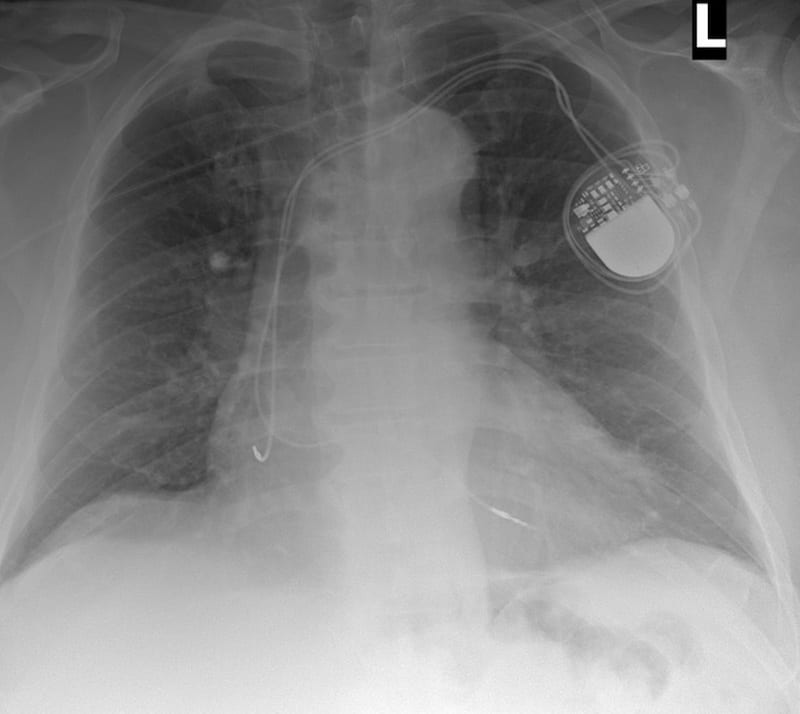

PA CXR INTERPRETATION

PA chest x-ray with appropriate penetration, exposure, with some rotation.

A dual chamber pacemaker is in-situ with atrial and ventricular leads noted, it is possible the ventricular lead crosses high, but overall position looks OK.

The right costophrenic angle is not fully visualised, but the left costophrenic angle is clear.

There is cardiomegaly with the cardiothoracic ratio ~0.6.

There is no visible pneumothorax.

There is an oblique artefact across the upper thorax likely either oxygen tubing or monitoring cable.

But we’re concerned about the lead position given our ECG findings and the PA CXR hasn’t really helped…